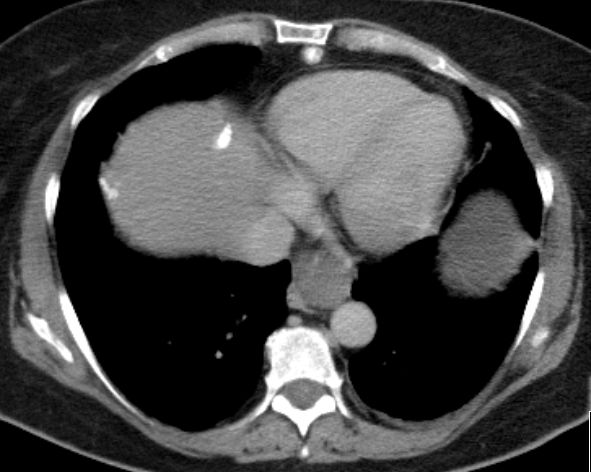

| Fall 1 | 51-jährige Frau mit primärem Peritonealkarzinom. | |||

| Therapie: Partielle Peritonektomie, HE mit Adnexen, Sigmaresektion (Hartmann), Omentumresektion. | Histologisch: Gut differenziertes seröses Adenokarzinom mit massenhaft Psammomkörperchen (Psammokarzinom). G1.Staging: pT3c. | |||